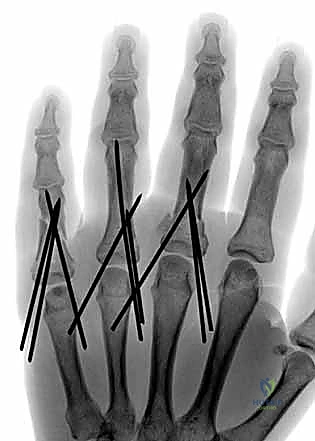

- ظاهرة تداخل الأصابع (Scissoring): وهي من أهم العلامات السريرية التي يبحث عنها د. هطيف. عند محاولة المريض إغلاق يده (صنع قبضة)، يتقاطع الإصبع المكسور فوق أو تحت الإصبع المجاور بدلاً من أن يشير بشكل متوازي نحو العظم الزورقي في المعصم. هذا يدل على وجود تشوه دوراني يجب تصحيحه جراحياً.

- التصوير بالأشعة السينية (X-rays): هو المعيار الذهبي لتشخيص كسور السلاميات. يطلب الدكتور هطيف دائماً ثلاث وضعيات أساسية:

- الأمامية الخلفية (AP View).

- الجانبية الحقيقية (True Lateral View): وهي الأهم لتقييم مقدار الانزياح الزاوي.

- المائلة (Oblique View): تساعد في رؤية الكسور الشعرية الدقيقة أو الكسور المفصلية الخفية.